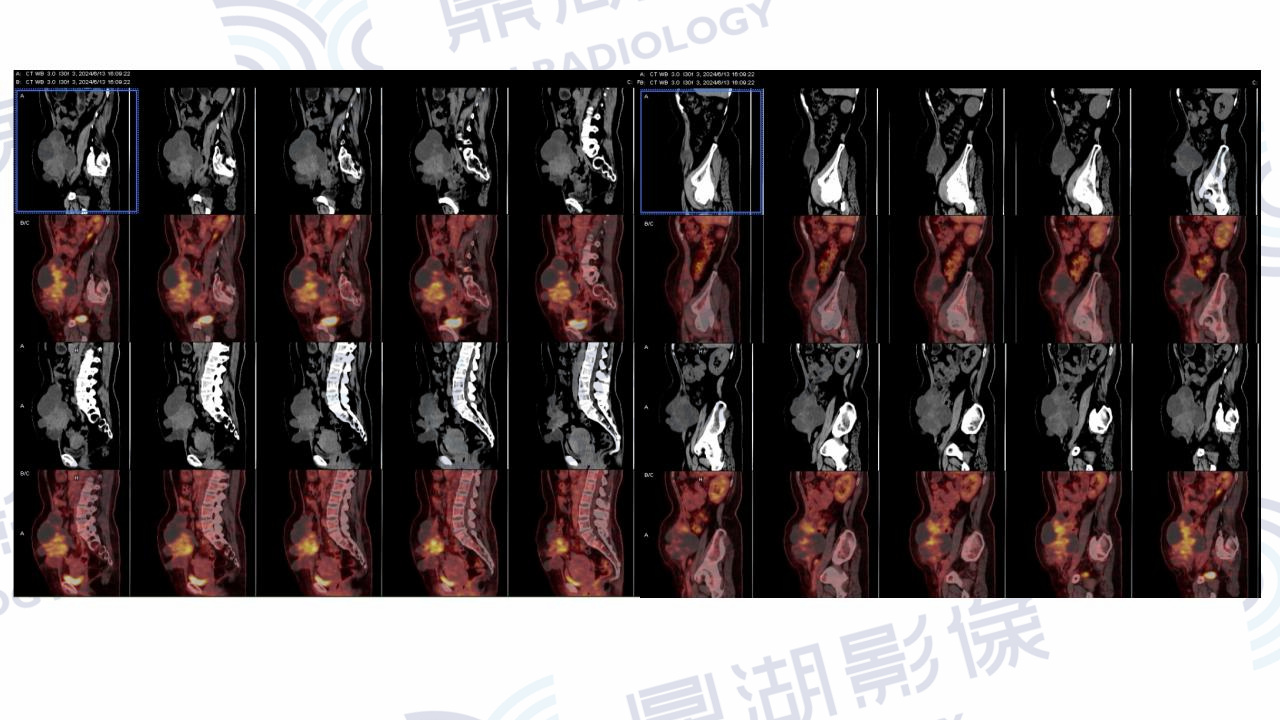

腹壁透明细胞癌

患者于一年前出现腹痛,查体提示右下腹包块,未行治疗。一年后复查腹部肿块增大,肿瘤标志物未见异常。剖宫产及腰椎间盘突出手术史。